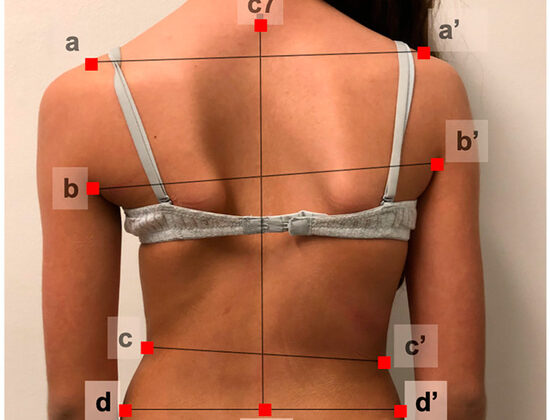

إذا لاحظتِ أن ابنتك لم تمر بعد بمرحلة البلوغ، يُنصح بالقيام بفحص مبكر للعمود الفقري، خصوصًا عند ظهور علامات الانحناء مثل:

ميلان الكتفين أو الوركين

بروز أحد جانبي القفص الصدري

تفاوت طول الأرجل

المتابعة الدورية: فحص العمود الفقري كل 6 أشهر، خصوصًا عند بدء مرحلة البلوغ أو ملاحظة أي تغير في استقامة الظهر.